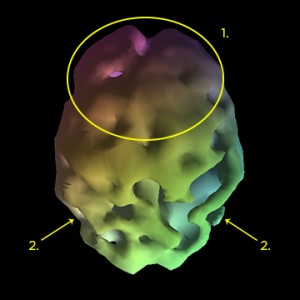

Alzheimerjeva bolezen predstavlja približno 60-80 % vseh demenc. Zanjo je značilen možganski vzorec, ki se kaže v znižani možganski aktivnosti v posteriornem predelu cingulate gyros ter v parietalnem in temporalnem predelu. V kasnejšem stadiju Alzeimejeve bolezni pa je opažena znižana možganska aktivnost tudi v drugih možganskih predelih, vključno z frontalnim.

1. znižana možganska aktivnost v frontalnem predelu, kar je značilnost že napredujočih stadijev bolezni;

2. znižana možganska aktivnost v parietalnih predelih.